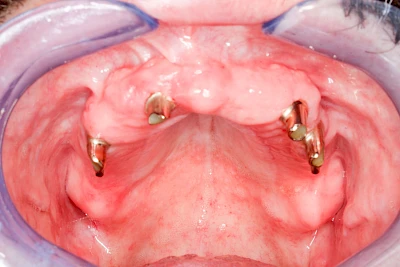

Bei herausnehmbaren Prothesen werden Implantate eingesetzt, um den Halt und den Tragekomfort der Prothesen zu verbessern. Dazu kommen verschiedene Verbindungselemente zum Einsatz:

- Teleskope

- Kugelköpfe

- Tellerförmige Lokatoren

- Stege

- Magnete (selten)

Neben rein implantat-getragenen zahnärztlichen Versorgungen werden bei herausnehmbaren Prothesen Implantate auch in Sinne einer "strategischen Pfeilervermehrung" ergänzend zu eigenen Zähnen zur Verankerung eines Zahnersatzes genutzt.

Varianten zur Verankerung von abnehmbarem Zahnersatz auf Implantaten